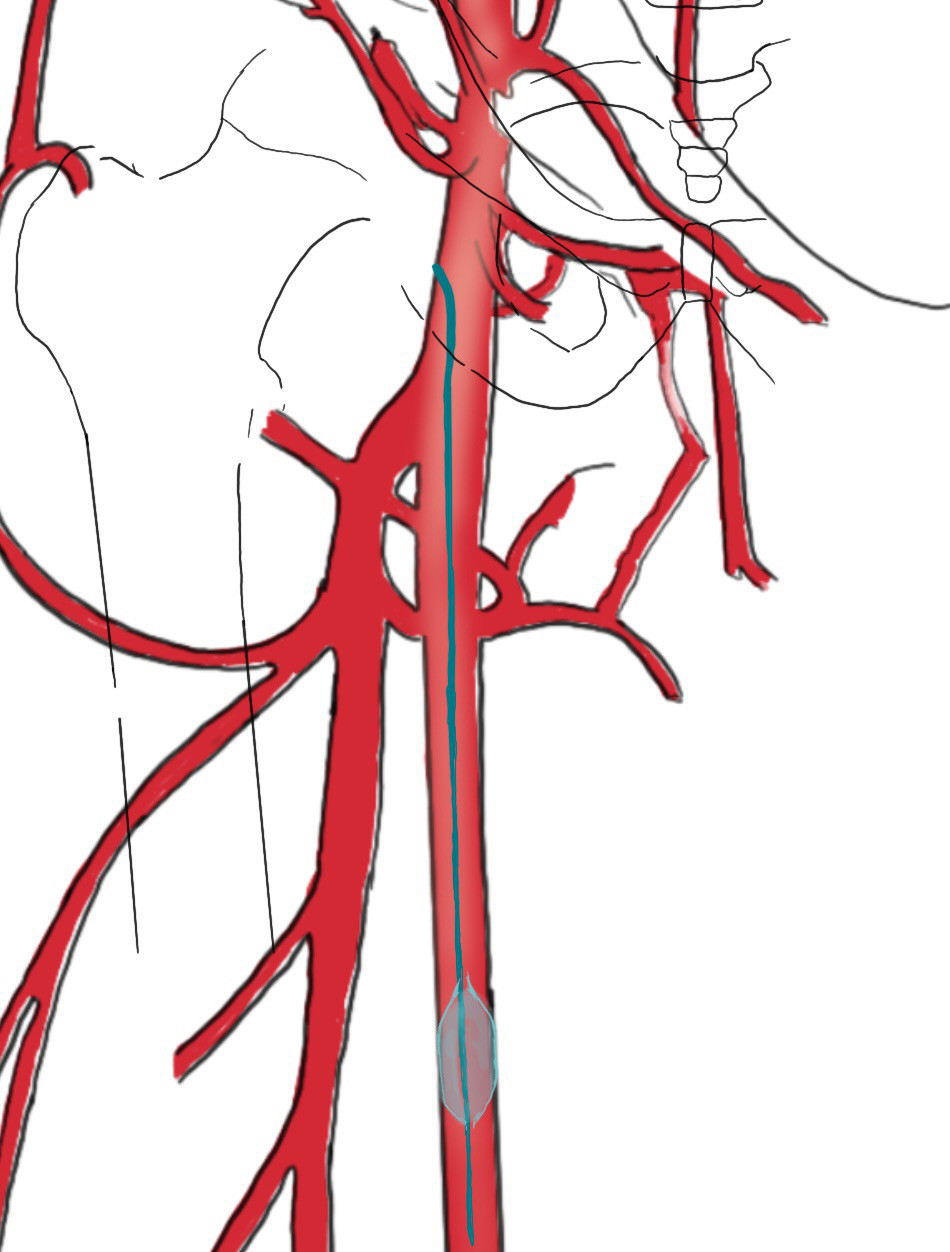

開腹手術にて動脈が3箇所傷あり止血処置